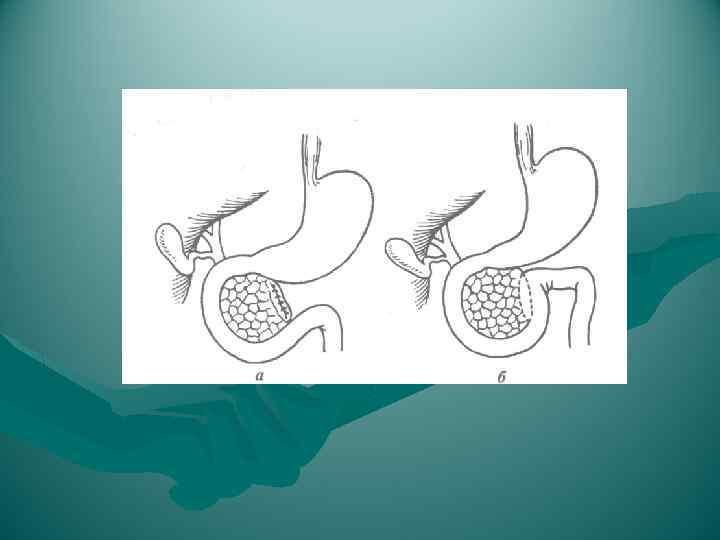

Холецистогастростомия

Холецистогастростомия

1) между желудком и поперечной ободочной кишкой, через желудочно-ободочную связку; этот способ самый удобный и его применяют чаще всего для обнажения всей передней поверхности поджелудочной железы; 2) через малый сальник; такой подход менее удобен и применяется редко, главным образом при опущении желудка; 3) через брыжейку поперечной ободочной кишки слева от позвоночника; этот доступ иногда применяют при кистах поджелудочной железы.

1) между желудком и поперечной ободочной кишкой, через желудочно-ободочную связку; этот способ самый удобный и его применяют чаще всего для обнажения всей передней поверхности поджелудочной железы; 2) через малый сальник; такой подход менее удобен и применяется редко, главным образом при опущении желудка; 3) через брыжейку поперечной ободочной кишки слева от позвоночника; этот доступ иногда применяют при кистах поджелудочной железы.